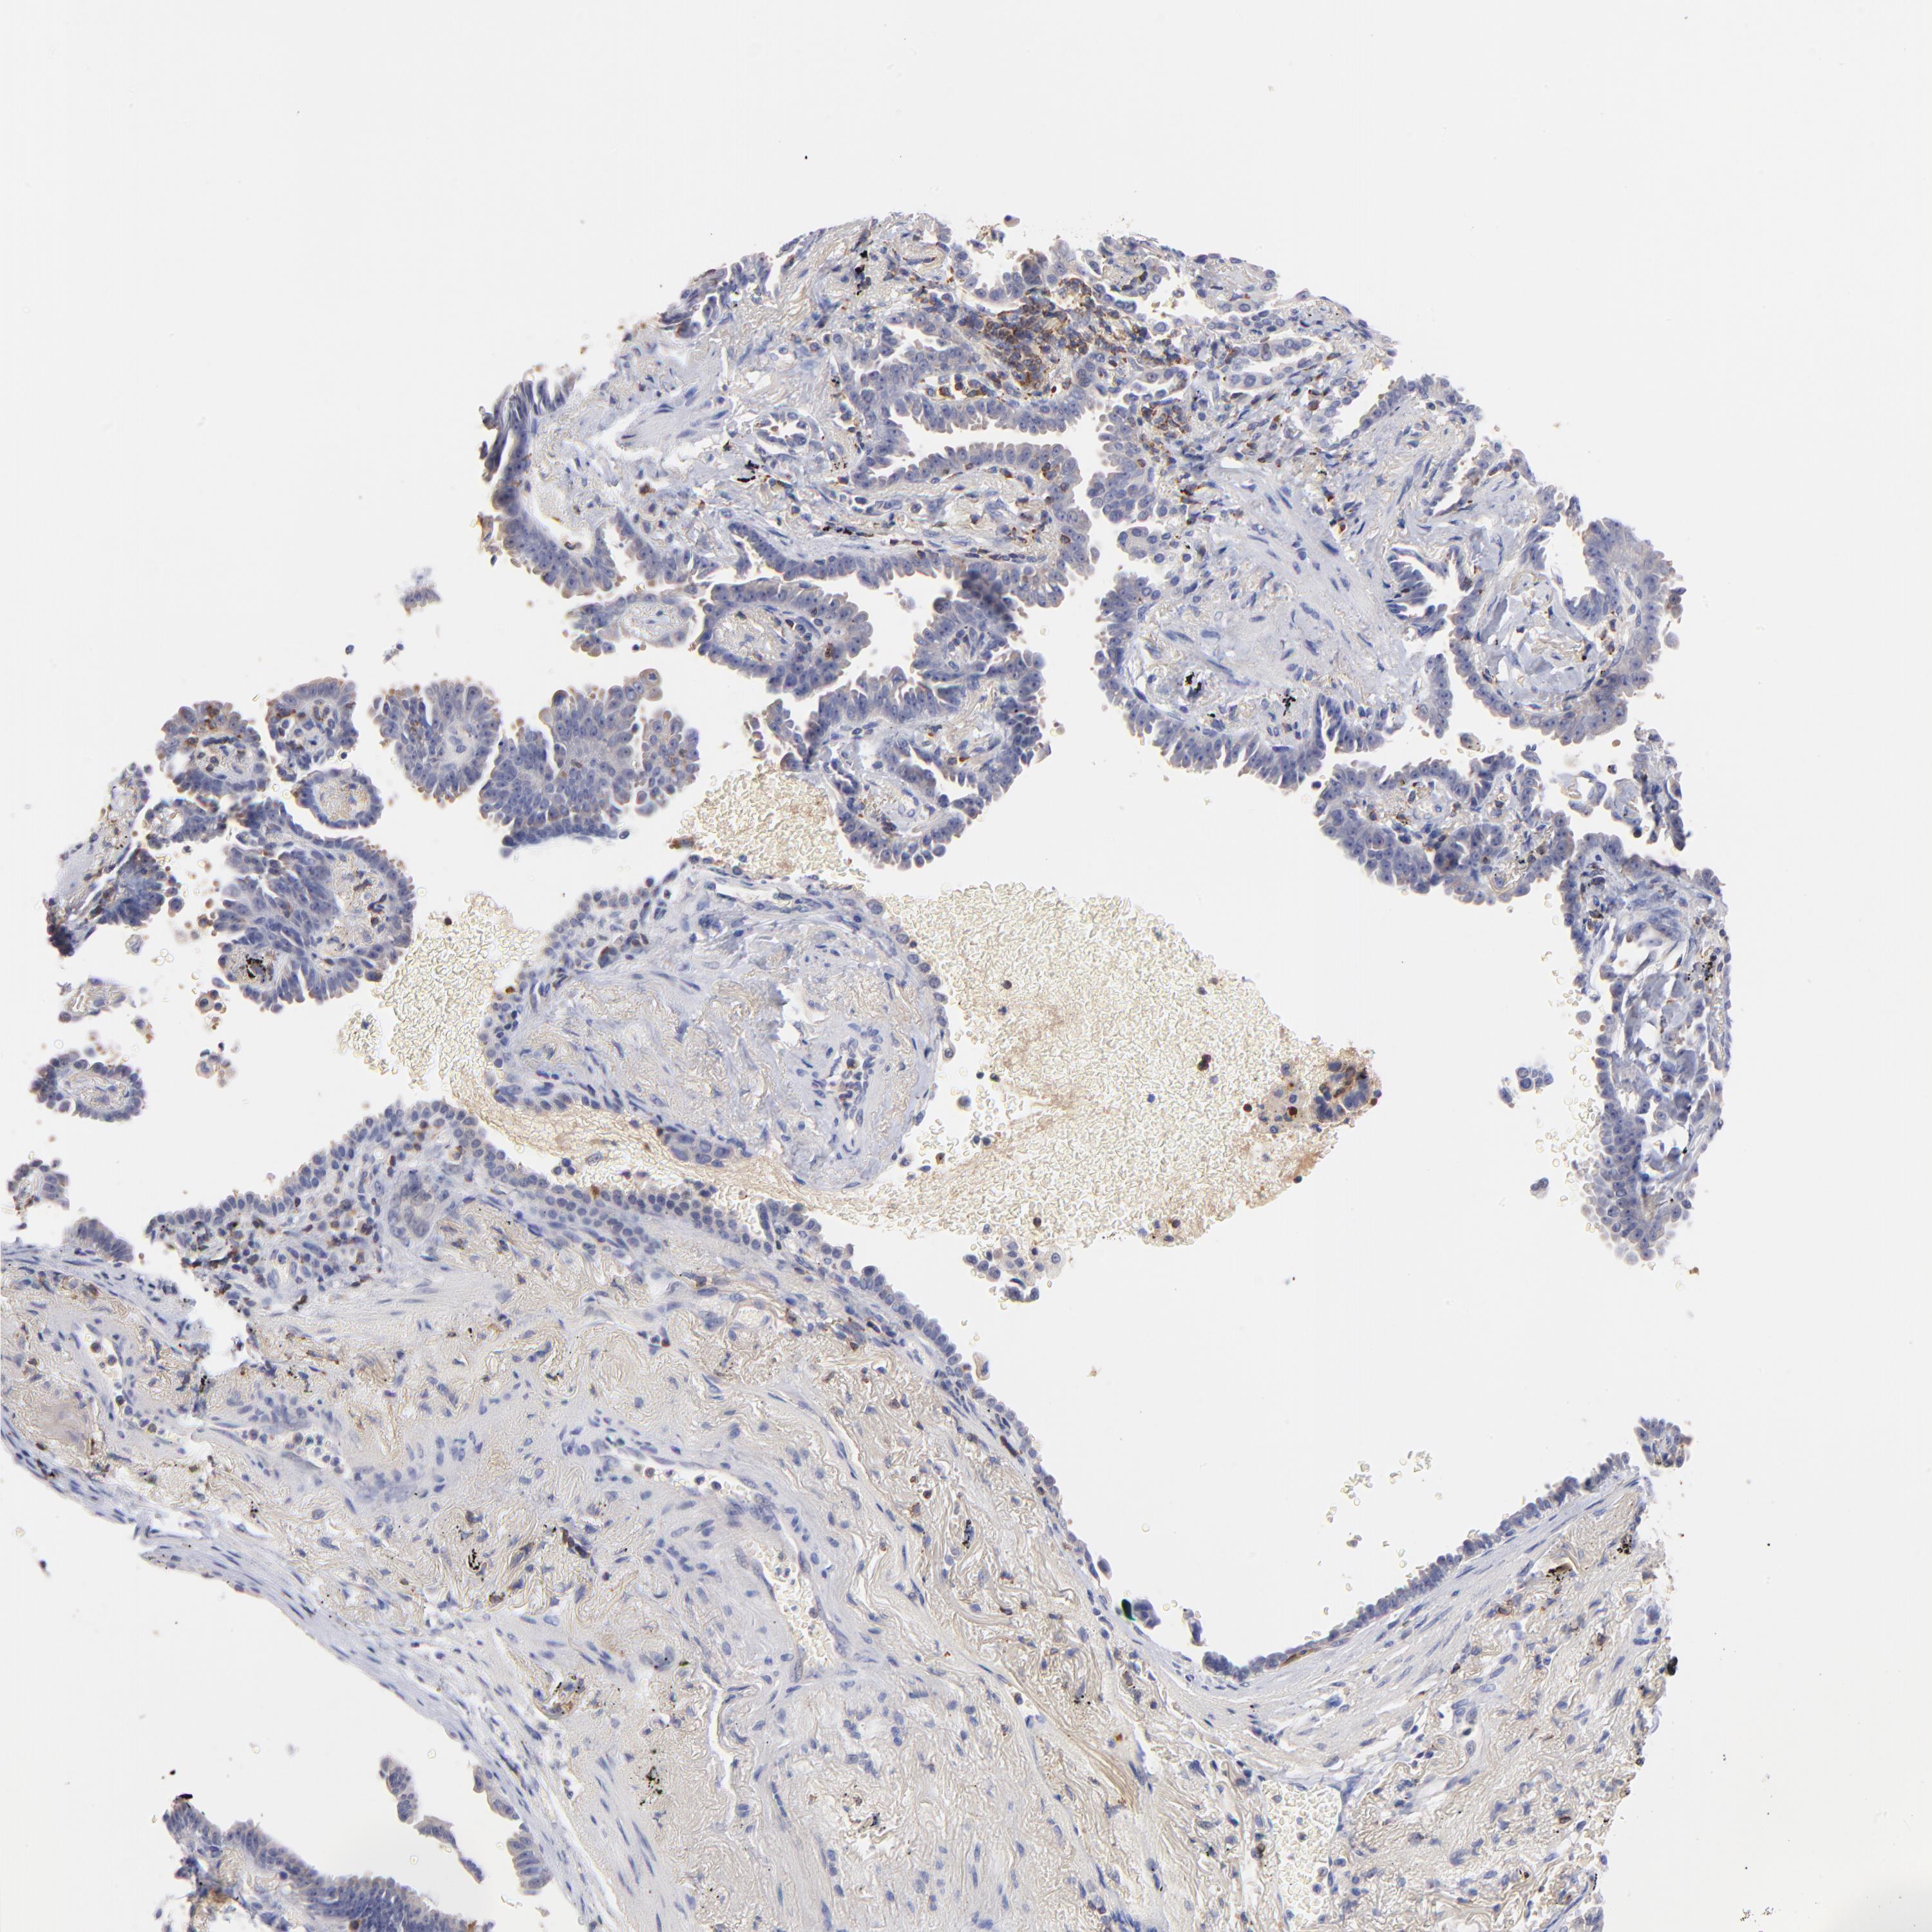

CANCER LUNG CANCER Show tissue menu

KREMEN2 is potential prognostic, high expression is unfavorable in Lung Adenocarcinoma (TCGA)

KREMEN2 is not prognostic in Lung Adenocarcinoma (validation)

KREMEN2 is not prognostic in Lung Squamous Cell Carcinoma (TCGA)